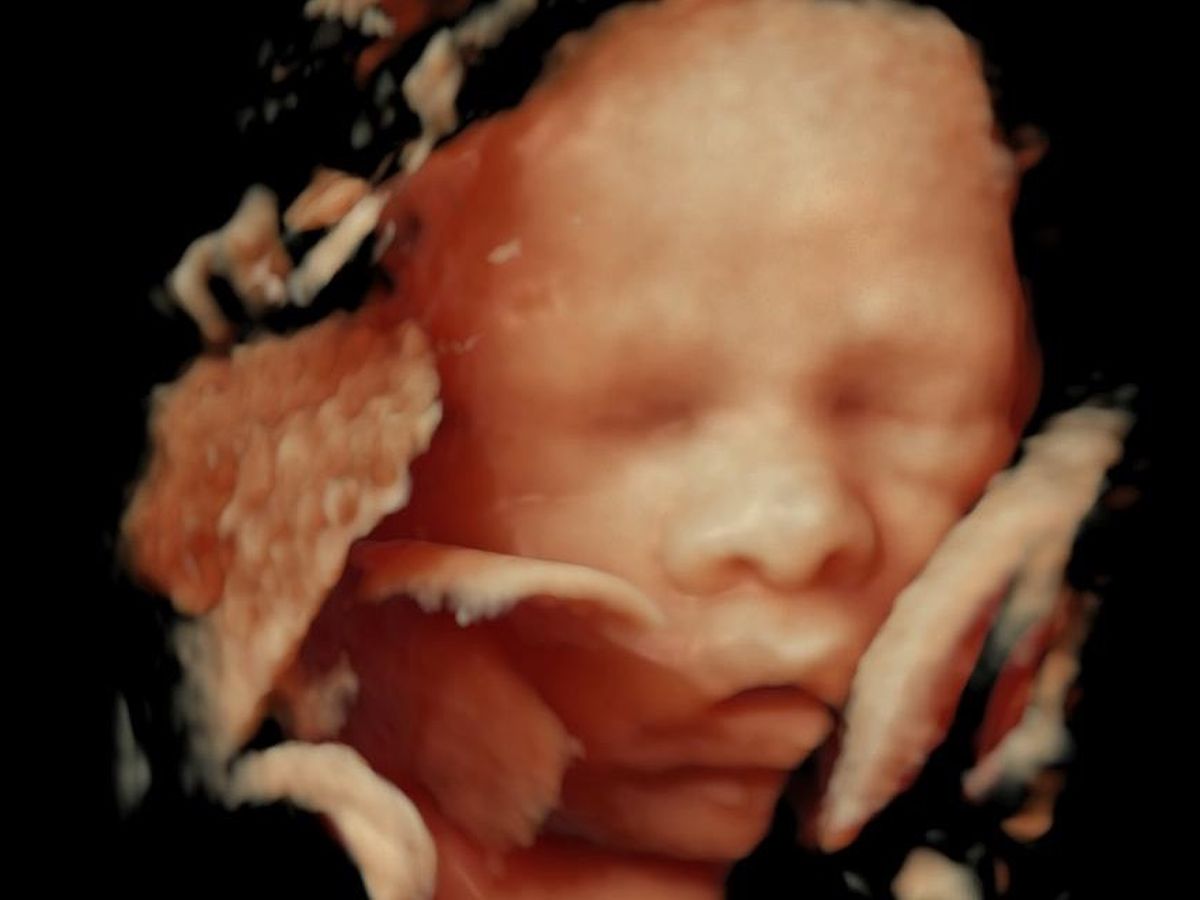

Hola, les contamos la historia de Thiago, es nuestro tercer embarazo ya que los otros dos no llegaron a término, por eso Thiago es un bebé muy deseado y amado, en el momento en el que decidimos intentar una tercera vez, estábamos decididos de que si no se podría, no se intentaría más. Pero cuando supimos que venía en camino fuimos las personas más felices y hemos tratado de ser lo más cuidadosos con el embarazo para asegurar que salga todo bien.

En nuestro último examen médico detectaron un quiste pulmonar en Thiago, el cual puede que se tenga que operar apenas nazca, lo que incrementa los costos médicos, razón por la cual decidimos abrir esta forma de ayuda, para asegurar que todo salga bien con Thiago en caso de necesitar esta cirugía en su pulmón, para que él esté bien y feliz con papá y mamá.

Hello, let me tell you the story of Thiago, it is our third pregnancy since the other two did not come to term, that is why Thiago is a very desired and loved baby, at the moment we decided to try a third time, we were determined that If it couldn't be done, it wouldn't be tried anymore. But when we found out that it was on the way, we were the happiest people and we have tried to be as careful as possible with the pregnancy to ensure that everything goes well.

In our last medical examination they detected a lung cyst in Thiago, which may have to be operated upon as soon as he is born, which increases medical costs, which is why we decided to open this form of help, to ensure that everything goes well with Thiago in in case he needs this surgery on his lung, so that he is well and happy with mom and dad